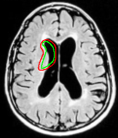

Refer to captionRefer to captionRefer to caption(a)(b)(c)Refer to captionRefer to captionRefer to caption𝑎𝑏𝑐\begin{array}[]{ccc}\includegraphics[width=72.26999pt]{tumor-init.pdf}&\includegraphics[width=72.26999pt]{tumor.pdf}&\includegraphics[width=72.26999pt]{tumor-edge.pdf}\\ (a)&(b)&(c)\end{array}

Figure 16: (a) Initialization with ring template, (b) converged snake and (c) edge detector output of image.

We next develop templates for objects with hole(s) in their structure. These templates are called ring templates. Figures 15 and 16 show examples of ring templates. The area enclosed between the red contours act as region 1subscript1\Re_{1} and the area between the green contours is region 0subscript0\Re_{0}. Figure 17 shows the construction of the ring contours. The two seemingly unconnected contours are actually one connected contour. Hence, partial derivative calculations in equation (26) are still valid.

In Figure 15, the ring template has been used for segmenting the left ventricular (LV) wall of heart in cardiac MR images. Another example is shown in Figure 16. The template used in both examples has a greater thickness in the inner ring-shaped annular region than the outer annular region. This was done to facilitate obtaining the desired object’s structural information by means of the contrast (for example, between the endocardium and the LV wall) that a good initialization can offer. Hence, while designing a template, we can incorporate prior knowledge of the object and its surroundings.